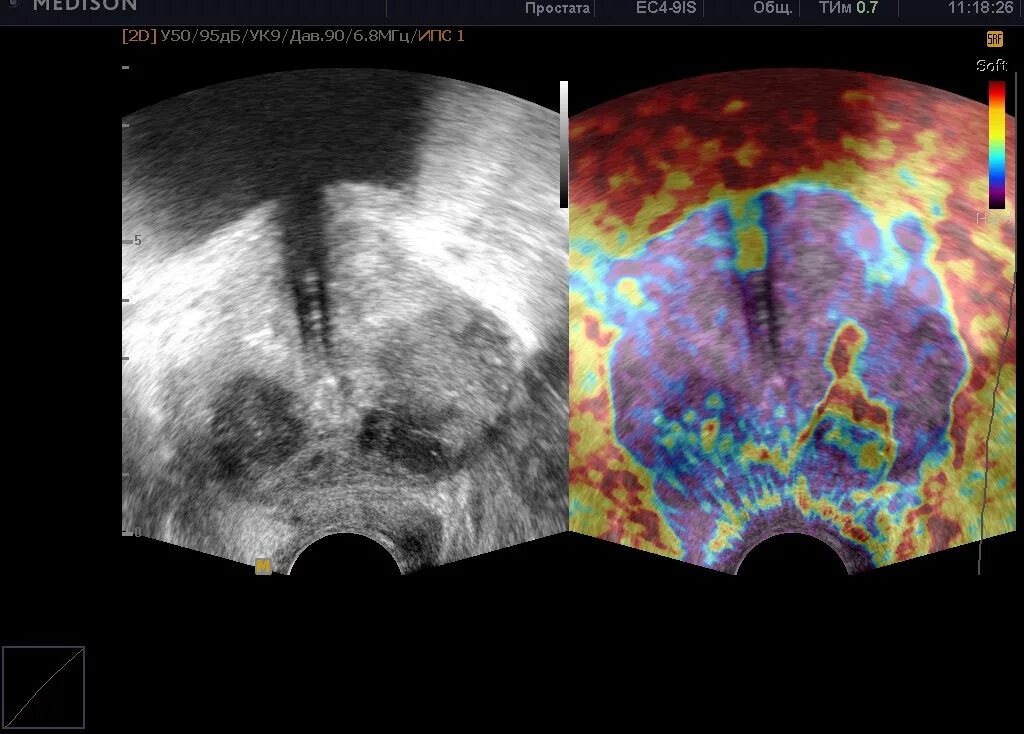

Нарезка простата